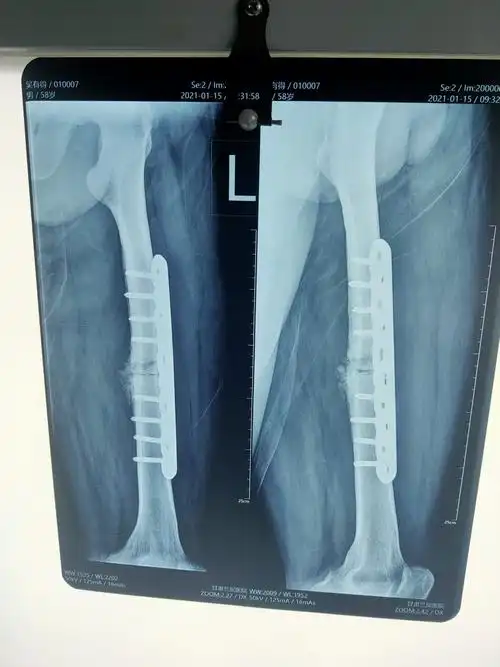

术后三月复诊,拍片显骨折断端愈合良好!